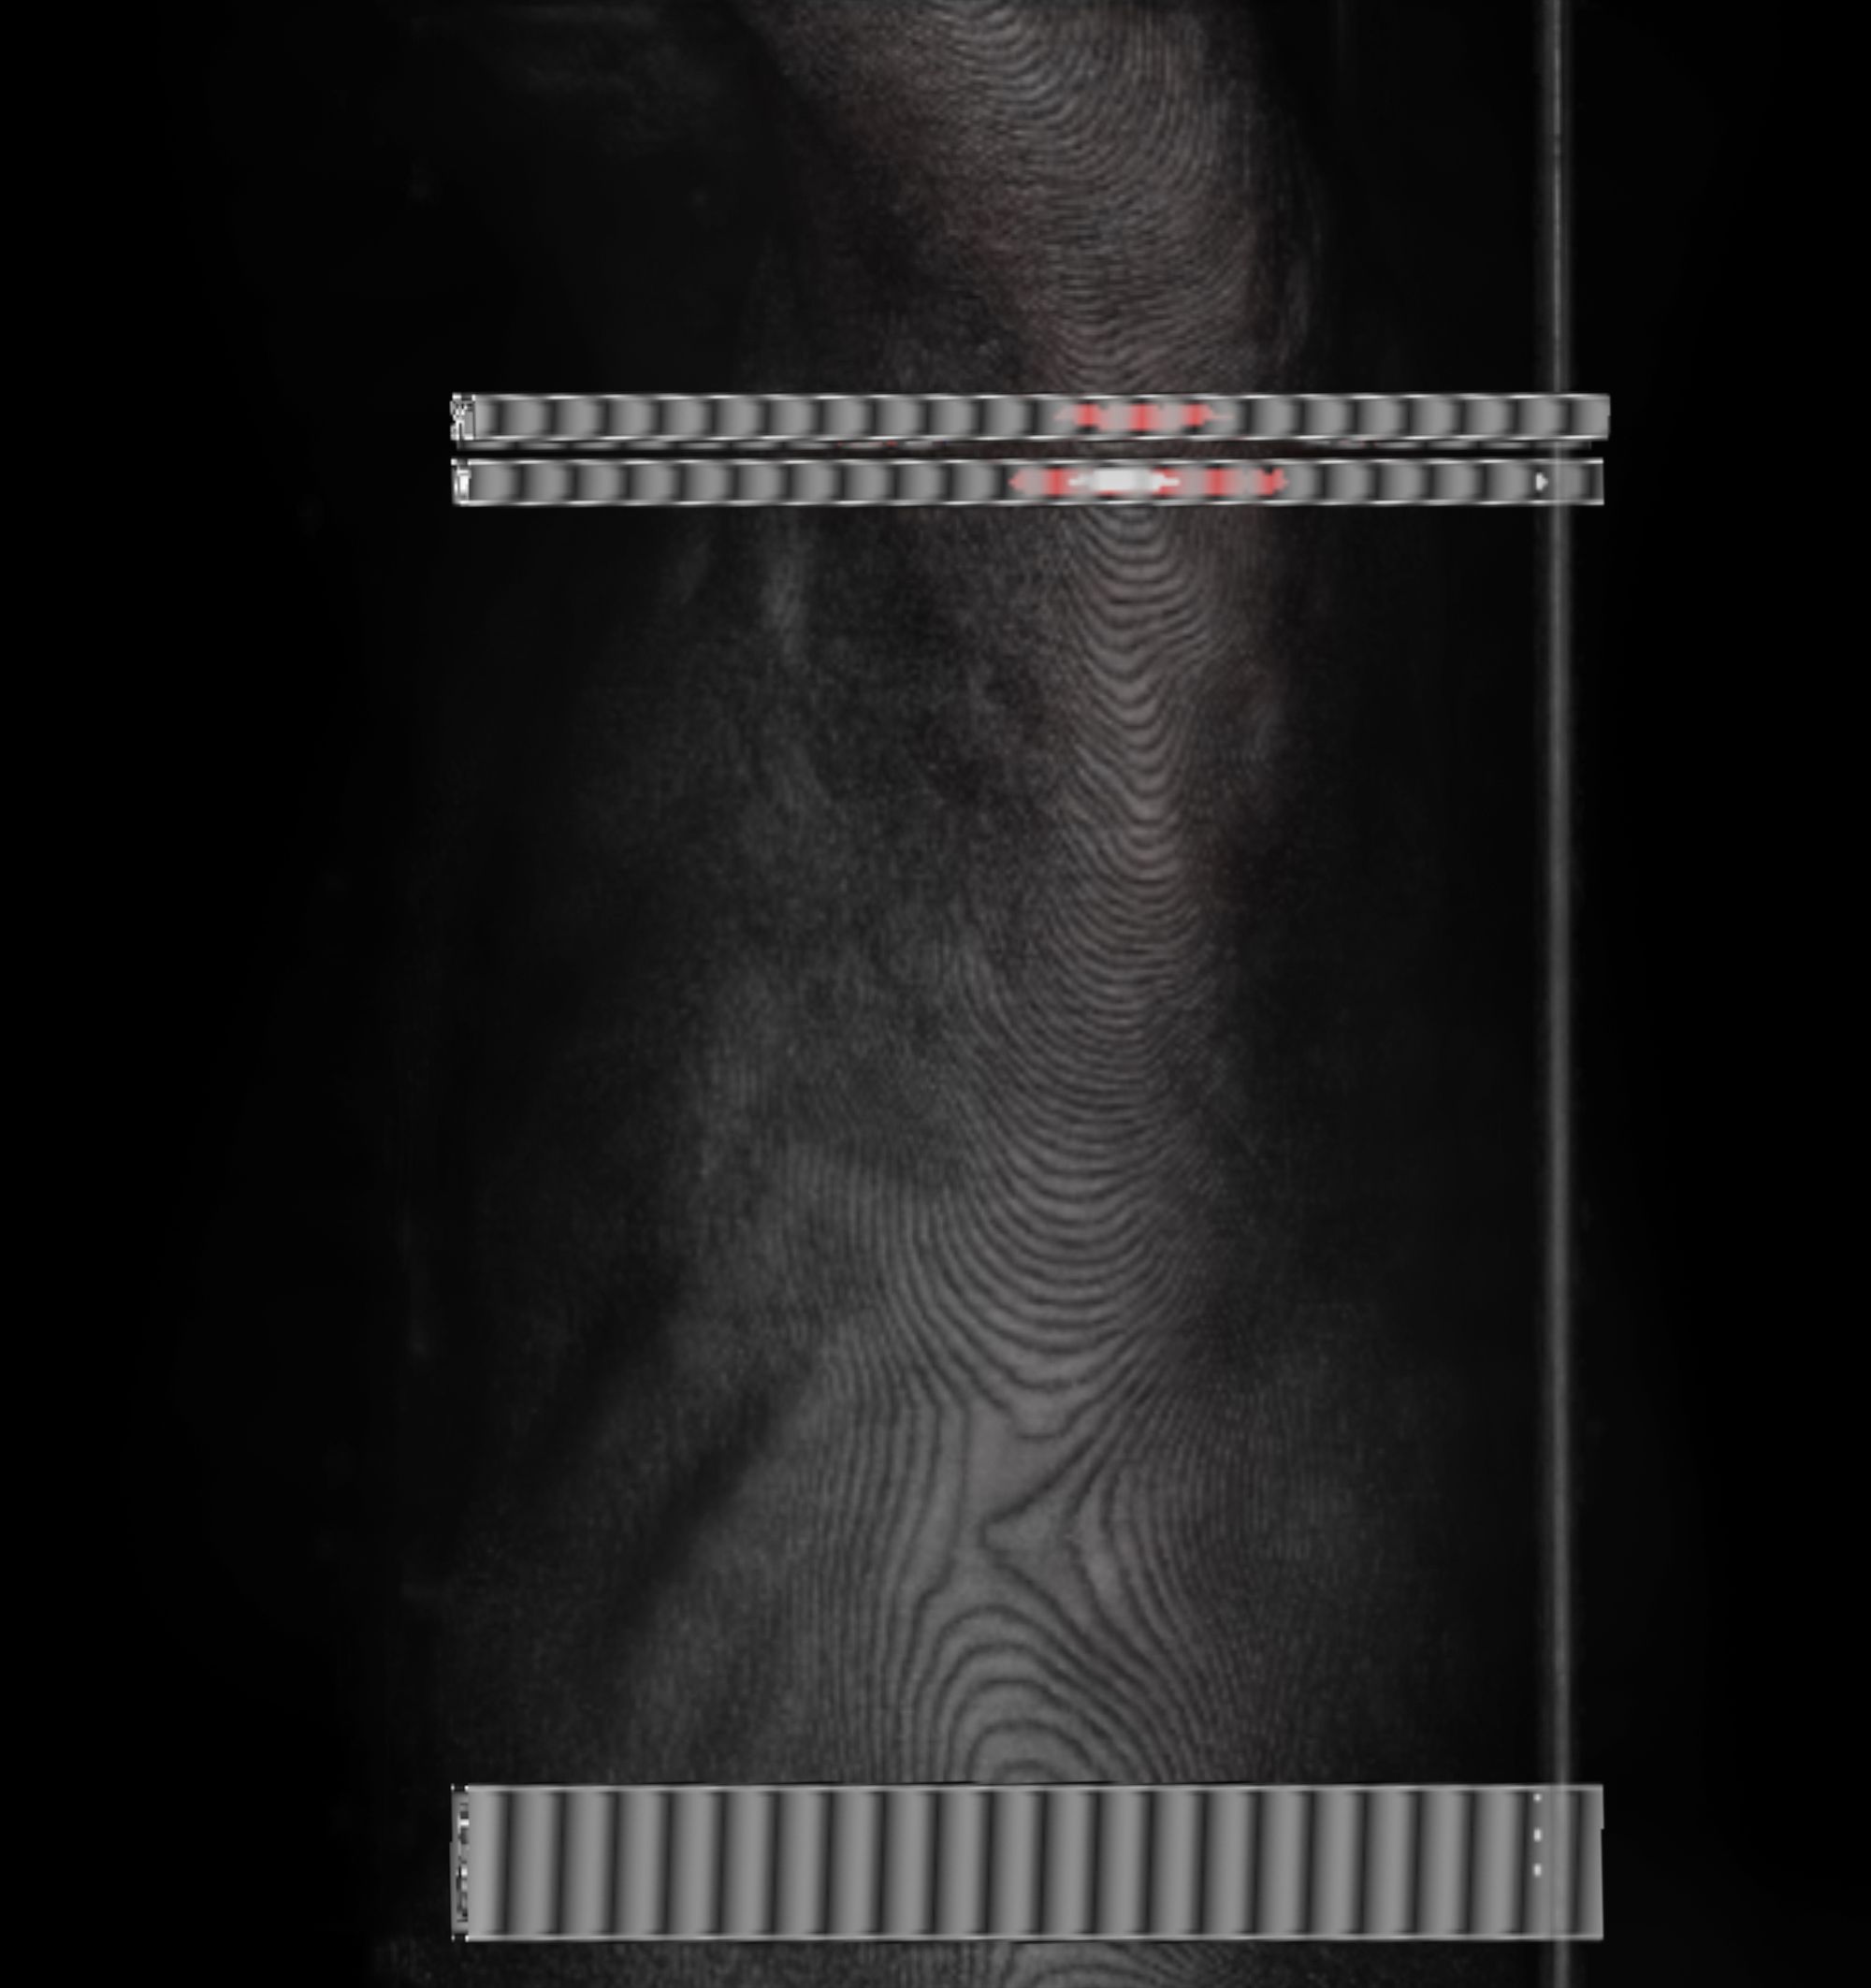

Chasing Intensities considers the body through its relationship to contemporary medical imaging technologies.

In this project, I look at the visual limit between the inside and the outside, the inner and the outer. I combine different visual approaches to materialise the body, using medical imagery, photography from manuals and radiology software. Decontextualised from their origin, these images speak of medicine’s relationship to both sex and violence, and remind us that, in medicine, to go into the body is always to go into the image first.